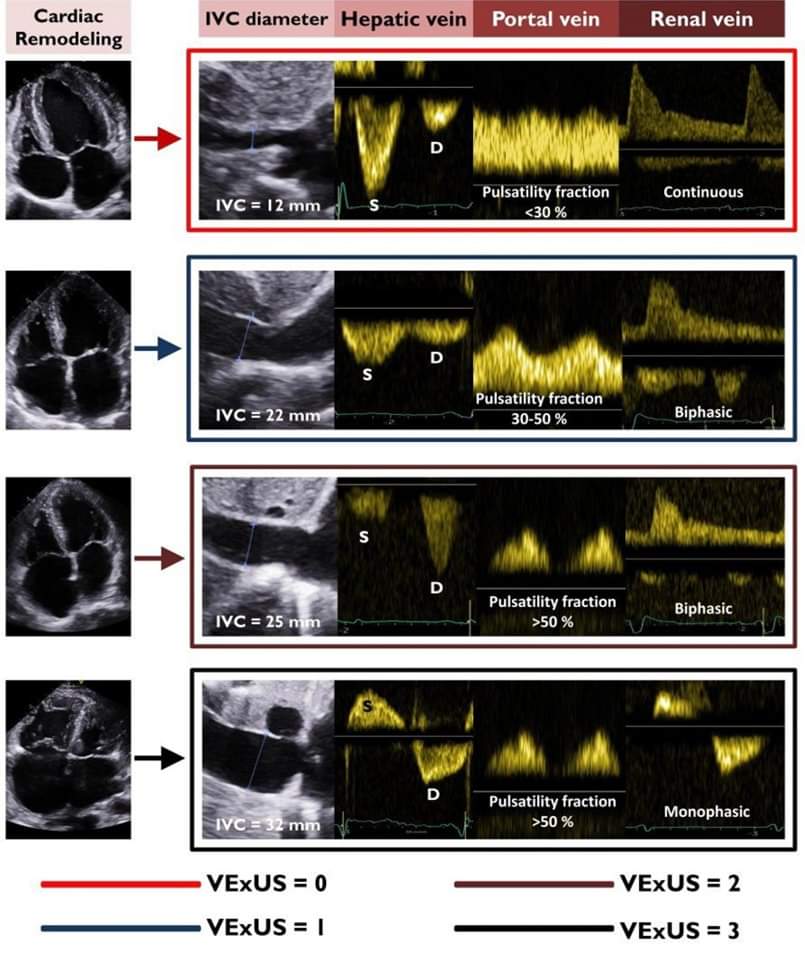

🔴Multiorgan Congestion Assessment by Venous Excess Ultrasound Score in Acute Heart Failure⤵️ #OpenAccess 🔹 https://t.co/jr9AkneY3P #Cardiology #FOAMed #MedEd #medstudent #paramedic #Cardiology #CardioEd #medtwitter #meded #CardioTwitter #cardiotwiteros #MedX